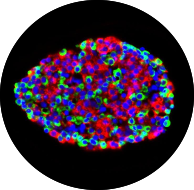

HumanIslets.com brings together five omics types and 74 in vivo and in vitro metadata for ~550 donors. This is the type of integrative, user-friendly tool that the Ewald Lab hopes to build!